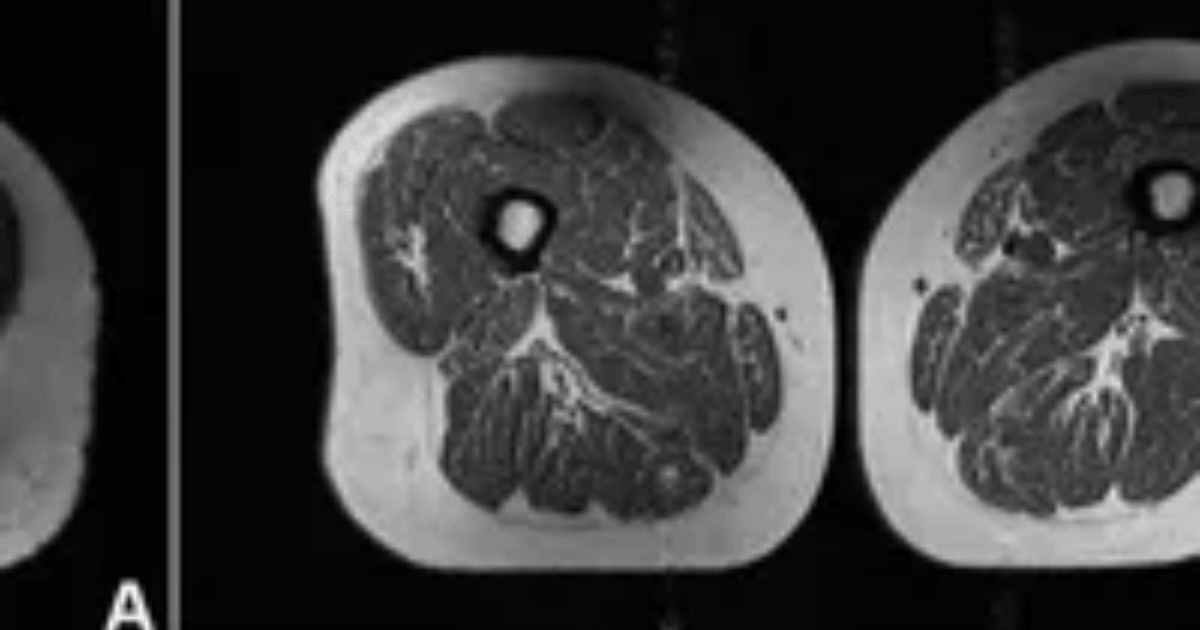

Dampak Makanan UPF Tubuh: Mengerikan! Potret Medis Ungkap Konsumsi Makanan Ultra-Proses Ubah Jaringan Paha Manusia Menyerupai Daging Berlemak!

retconomynow.com – Dunia medis kembali dikejutkan oleh visualisasi nyata mengenai pengaruh buruk pola makan modern…